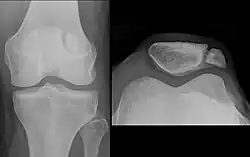

| A fracture of the patella seen on a lateral view | |

The patella can break in various ways depending on the way it is injured, and into two or more pieces.[1] Types include transverse, the most common, with one fracture line;[5] marginal; osteochondral; and the rare vertical type, or stellate, where a direct compression force gives rise to a comminuted pattern.[5][7] Patella fractures can be further classified as displaced, where the broken ends of bone do not line up correctly and separate by more than 2mm, or undisplaced and stable where pieces of bone remain in contact with each other.[1][7] If fragments of patella bone stick out from the skin it is known as an open patella fracture, and closed if the overlying skin is intact.[1]

Transverse fracture of patella -

Comminuted fracture of patella -

Osteochondral fracture of patella -

Vertical patella fracture